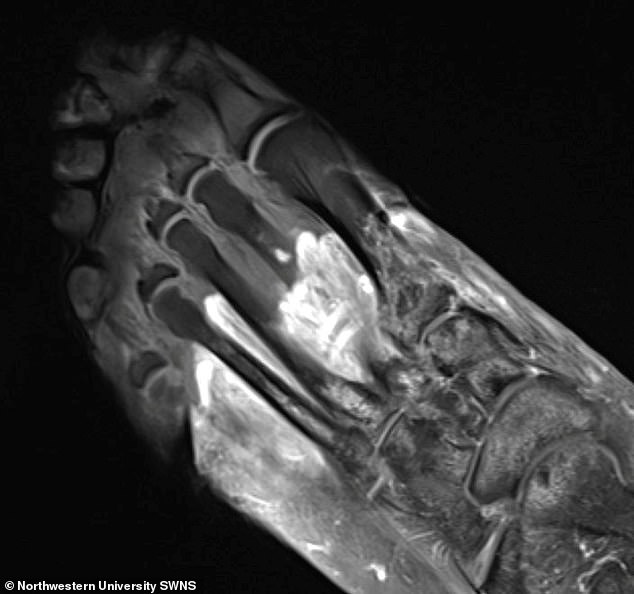

Ảnh chụp của một bệnh nhân COVID-19 cho thấy một phần bàn chân bị hoại thư.

Trong nghiên cứu của Đại học Northwestern, các nhà khoa học sử dụng các kỹ thuật hình ảnh khác nhau bao gồm chụp CT, MRI và siêu âm, để hình dung nguyên nhân gây hoại thư và các cơn đau cơ và khớp lâu dài ở bệnh nhân COVID-19.

Nói về hoại thư và các triệu chứng cơ và khớp khác trên phim chụp của bệnh nhân COVID-19, bác sĩ Deshmukh giải thích một số dấu hiệu chính.

Cô nói: "Chúng tôi nhận thấy mô bị phù nề và viêm (xuất hiện chất lỏng, sưng tấy), tụ máu hoặc mô tàn phế (hoại thư).

"Ở một số bệnh nhân, các dây thần kinh bị chấn thương; ở những người khác, lưu lượng máu bị suy giảm (cục máu đông)".